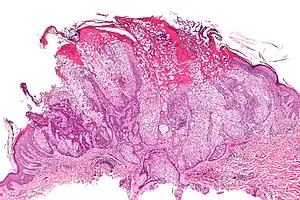

Micrograph of a sebaceous adenoma, as may be seen in Muir–Torre syndrome. H&E stain. | |